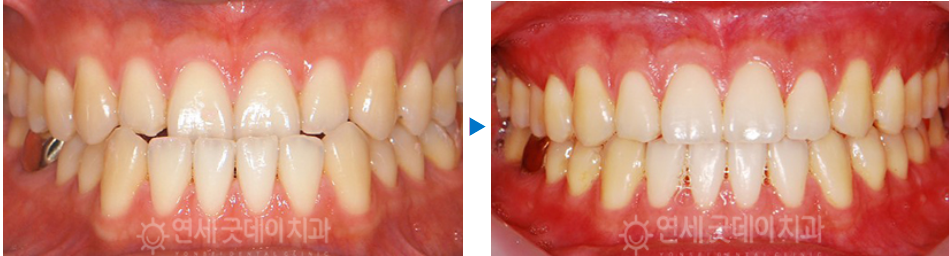

치료 후

저희 본원에 성실히 내원해주신 결과

위와 같은 결과를 보실 수 있었습니다.

확실히 치료 전에 비해 하관이 정돈된

느낌을 받을 수 있었고, 환자분께서도

많이 만족해 해주셨습니다.

치료 전 - 치료 후

치료 전과 후를 한번에 살펴보게 되면

주걱턱 성향의 전형적인 옆모습이 개선되고,

물리지 않던 송곳니가 잘 물리고 있는

모습을 볼 수 있는데요.

결국엔 모든 치아가 뒤로 감으로써 윗니가

아랫니를 살짝 덮는 정상교합이 완성되었습니다.